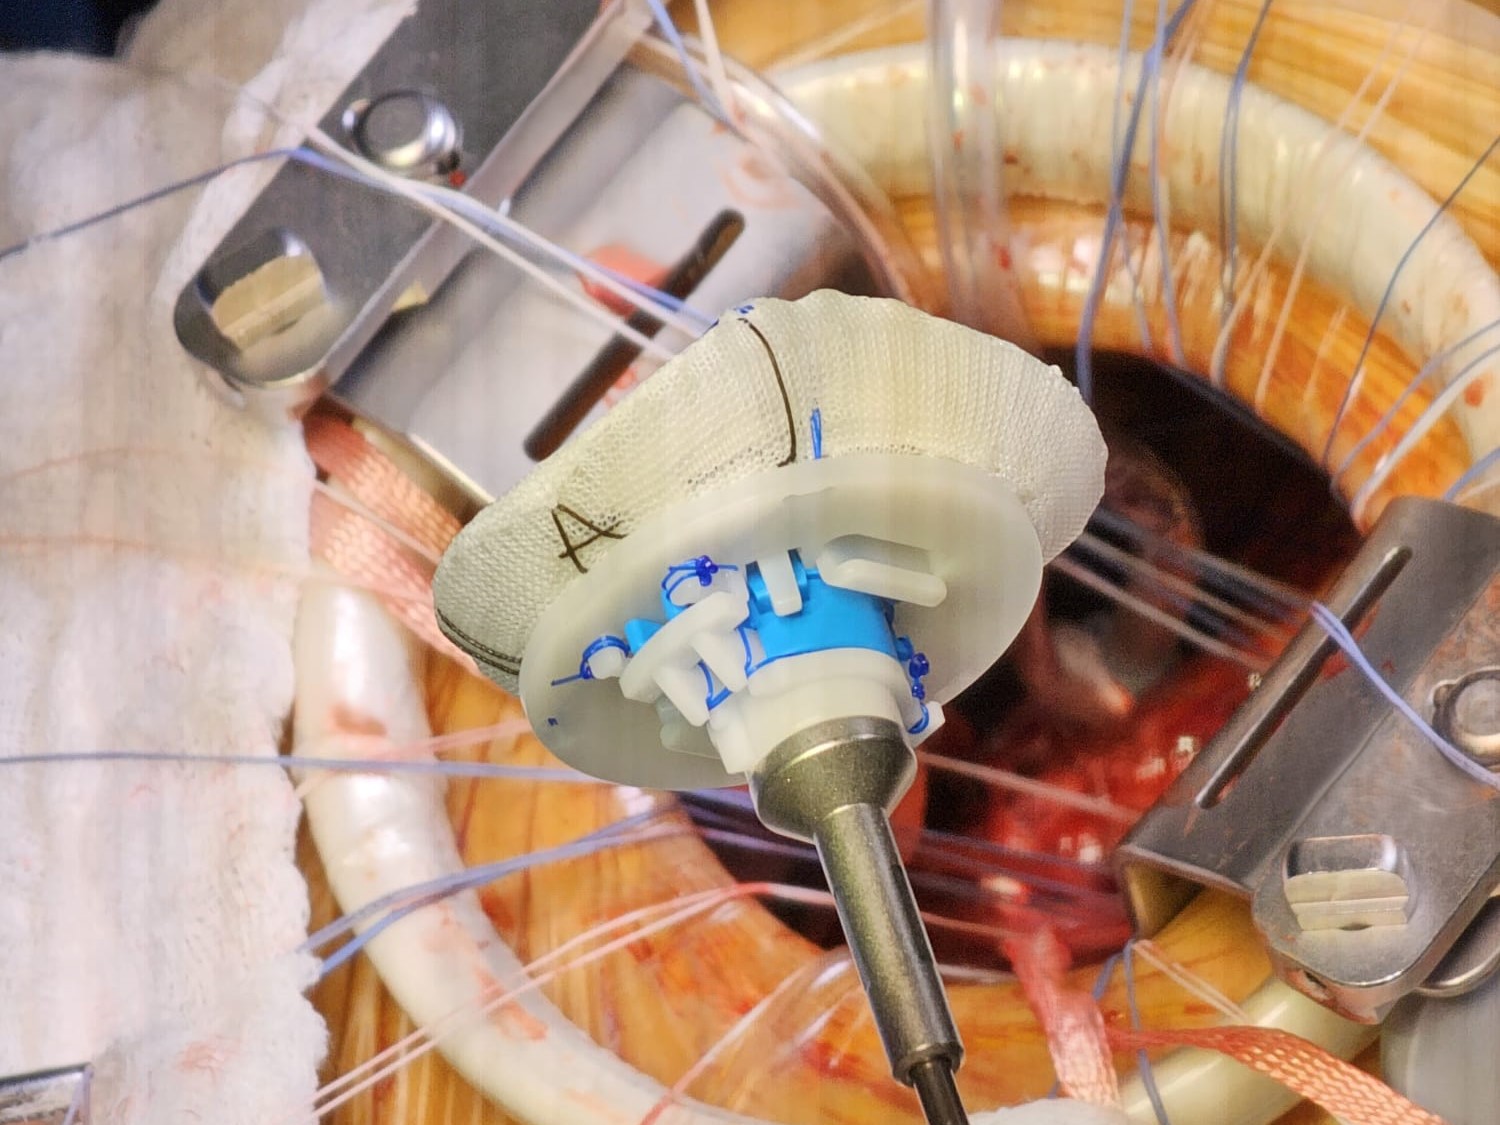

Procedura comuna în reparatia valvei mitrale o reprezinta anuloplastia cu inel. Anuloplastia se realizează prin montarea unui inel sintetic cu rolul de a reda si a stabiliza forma corectă a inelului valvei mitrale a pacientului.